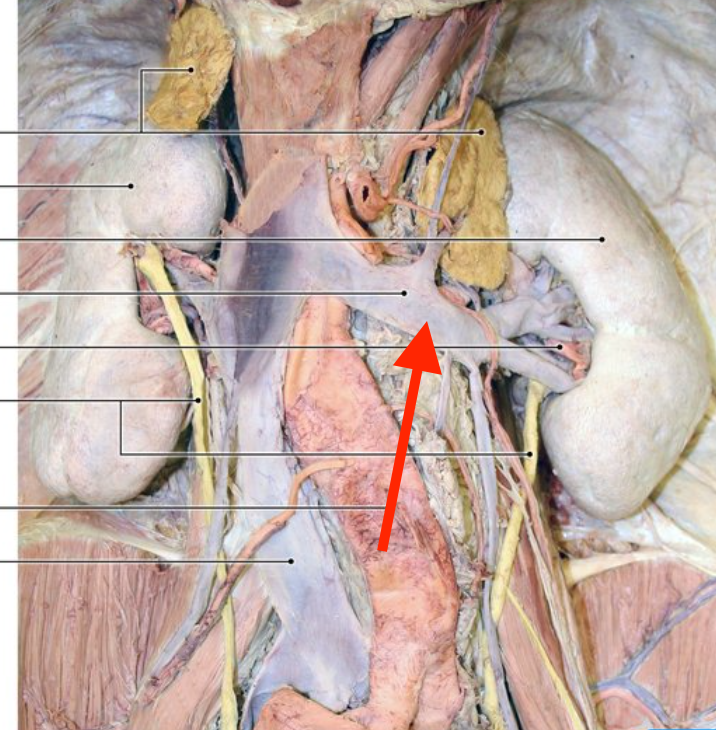

pararenal fat

perirenal fat

hilum (kidney)

left renal vein